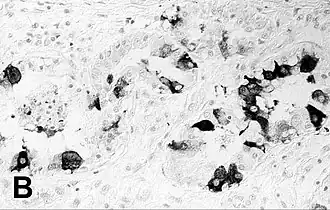

| Immunohistochemische kleuring van een geïnfecteerde zeehondenlong. | |||||||||